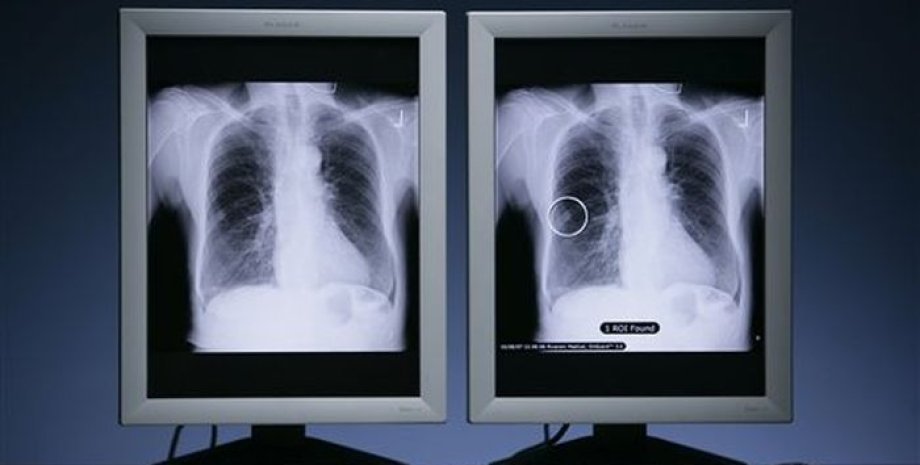

У жителя Италии медики обнаружили необычное заболевание: в его легких "выросли" плесневые грибы.

затем, после очередного тщательного обследования медики обнаружили в легких у больного самую настоящую грибницу, некоторые отростки которой достигали 8 сантиметров в длину.

Медики считают, что фермер мог занести себе в легкие грибковую инфекцию аспергиллез, работая в поле. Споры проникли в его дыхательные пути, а затем нашли благоприятную для себя полость и начали размножаться.